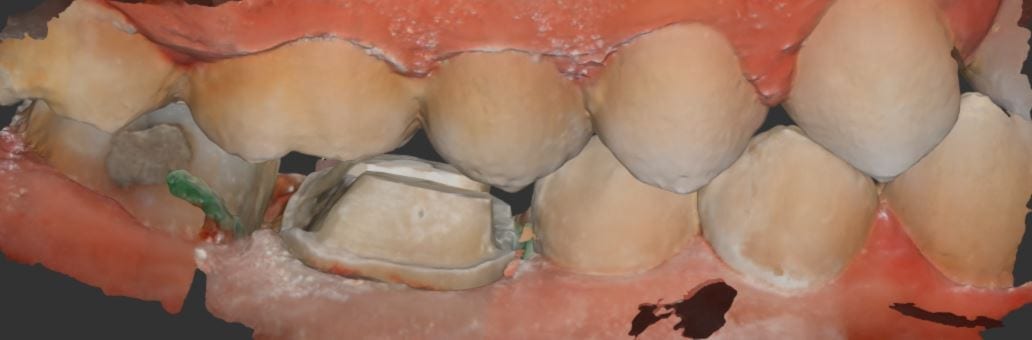

Another example of how well the i500 from Medit can scan with a deep focal length. This is impossible to do with any other IOS system on the market. Don’t […]